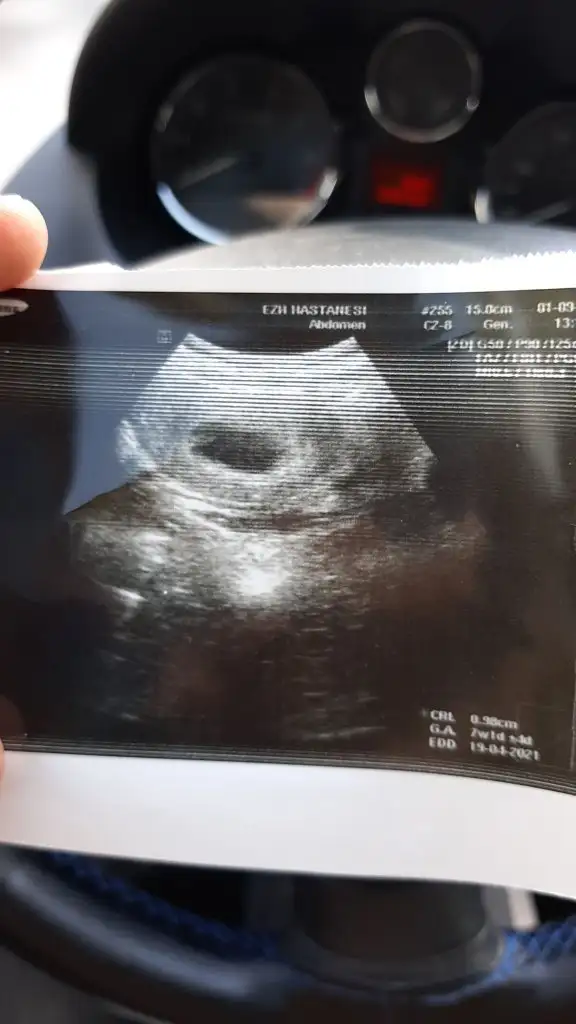

Karından bakıldı ise erkekBende yorum alabilir miyim

Karından bakıldı ise erkekHanımlar sizce

Evet karından bakıldı daha öncede atmıştım o zaman vajinaldi kız demiştiniz nubu merak ediyorum doğrusu o zamanda atarım inşallah teşekkürlerKarından bakıldı ise erkek

Evet en iyi nub Dr USG cihazı ile nasıl tutuyorsa o resmi alıyor sanırımEvet karından bakıldı daha öncede atmıştım o zaman vajinaldi kız demiştiniz nubu merak ediyorum doğrusu o zamanda atarım inşallah teşekkürler